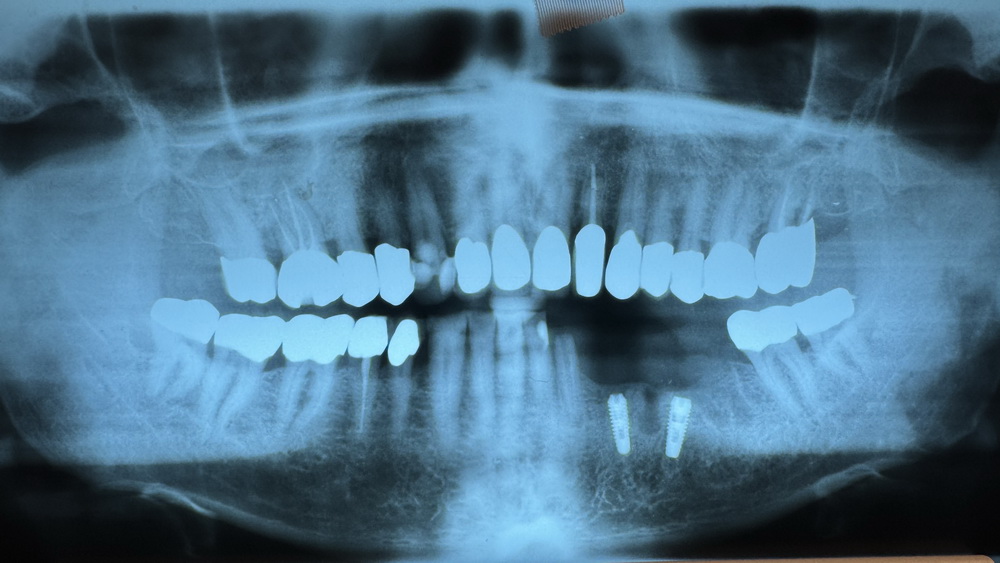

Durch das bewusst schräge Inserieren des Implantat 36 kommt die klinische Krone in regio 36 durch die schleimhaut hinduch. Die Implantate sitzen aber beide in möglichst gesundem Eigenknochen, statt das Implantat 36 in vorgeschädigten Knochen zu setzen, der erst mit einem neu zu bildenden Knochen hätte neu aufgebaut werden müssen.

Wenn man einen Bleistift in der Achse des hinteren Implantates anlegt, sieht man, dass der Implantataufbau, der das Zahnfleisch durchbricht, dann tatsächlich dort klinisch im Mund aus dem Zahnfleisch rauskommt, wo vohrer die natürliche klinische Zahnkrone saß. Dazu nutzt man dann einen geinkelten Impülantataufbau und "Fertig ist die Laube!"